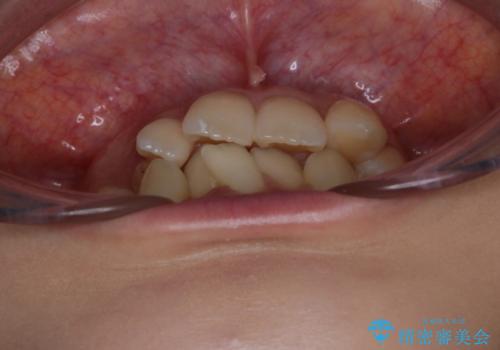

がたつきが強いガチャ歯。埋伏歯抜歯+矯正。すごいところに犬歯が埋まっていたのを抜いてワイヤー矯正治療

がたつきの強さから4本抜歯の必要性がありましたが、右上の歯は犬歯が一本埋まっており、乳歯がある状態でした。

右上については先に乳歯を抜歯して、犬歯が使えるようであれば第一小臼歯を抜歯することとして治療を開始しました。

当初、犬歯が動くようであれば代わりに小臼歯を抜歯する予定でしたが、

開窓して器具で力をかけても動く様子がなかったため抜歯とし、小臼歯を犬歯に見立てて治療を完了しました。